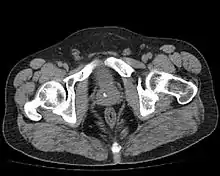

Диагноз устанавливается на основании пальцевого ректального исследования простаты, данных ультразвукового и рентгеновского исследования. При пальцевом ректальном исследовании выявляется плотный участок в ткани предстательной железы, в ряде случаев определяется крепитация. Возможно отсутствие каких-либо изменений при пальцевом исследовании простаты. Изменения, обнаруженные при исследовании предстательной железы пальцем, необходимо дифференцировать с раком и туберкулезом предстательной железы. При УЗИ простаты (трансректальном или трансабдоминальном) обнаруживаются гиперэхогенные участки в предстательной железе с формированием акустической дорожки. Размеры камней варьирует от 3 до 25 мм и более. Множественные камни наблюдаются примерно в 70 % случаев. При рентгеновском исследовании выявляют около 30 % камней предстательной железы, так как большинство камней рентгеннегативные[3]. В качестве дополнительных методов визуализации могут быть использованы КТ и МРТ таза. Наличие бессимптомных камней простаты само по себе не оказывает влияние на объём предстательной железы и уровень ПСА в сыворотке крови[7].